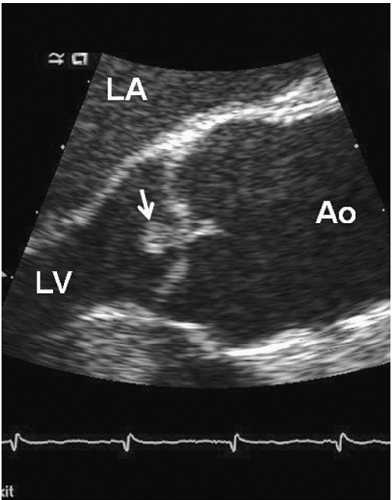

Lambl excrescences (valvular strands)

Small, filiform, fibrous strands at coaptation sites.

Typically seen on the aortic valve.

Can be mistaken for a mass.

<p>Small, filiform, fibrous strands at coaptation sites.</p><p>Typically seen on the aortic valve.</p><p>Can be mistaken for a mass.</p>